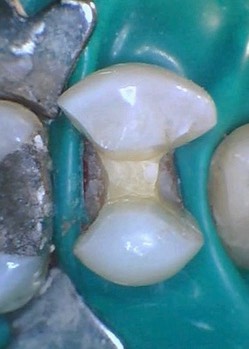

Mendel Sato #12 prep